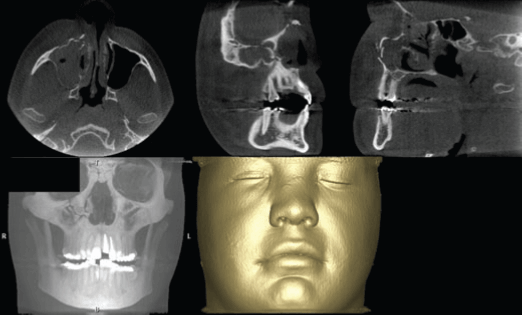

Fractura del proceso cigomático maxilar evaluado con tomografía maxilofacial

El examen por imágenes es un componente esencial del manejo de eventos traumáticos. Respalda todos los aspectos, desde el diagnóstico y la planificación del tratamiento hasta la evaluación de los resultados. Desafortunadamente, la cantidad de información obtenida de las radiografías simples convencionales o capturadas digitalmente es limitada por el hecho de que la anatomía tridimensional...